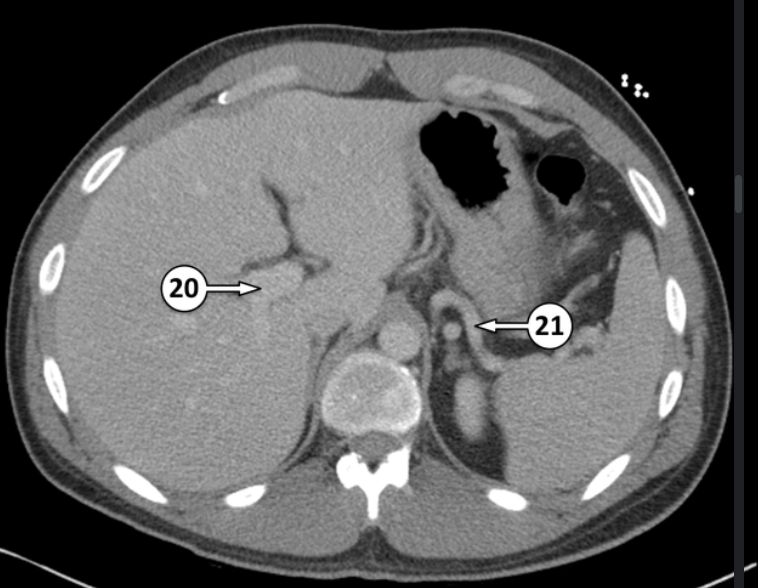

20 and 21 are both blood vessels. Label which blood vessels they are

right portal vein

right splenic artery